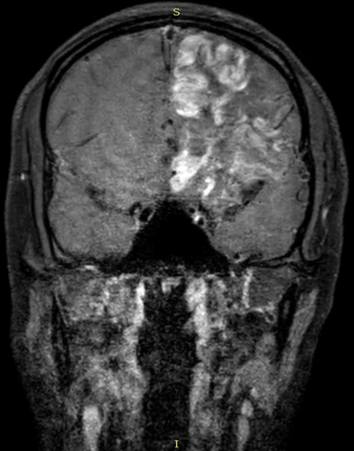

高分辨核磁血管壁增强成像:左侧颈内动脉C7段管壁可见强化影。

患者高分辨核磁血管壁成像未见动脉粥样硬化斑块的“偏心样”强化,同时颅外血管也无动脉粥样硬化证据,故考虑大动脉粥样硬化性可能性较小,但不能完全排除。患者青少年女性,有动静脉血栓病史(大脑中动脉血栓、肺动脉栓塞),多种抗磷脂抗体单次阳性,Coombs试验阳性,考虑抗磷脂综合征可能性大。因此,本例患者的病因考虑抗磷脂综合征可能性大,大动脉粥样硬化性不除外。治疗上,因患者梗死面积较大,复查CT梗死灶渗血,未使用华法林抗凝,暂予以依诺肝素抗凝、吗替麦考酚酯免疫治疗。同时建议12周后复查凝血功能、抗磷脂抗体等,根据情况调整抗凝方案及免疫治疗方案。